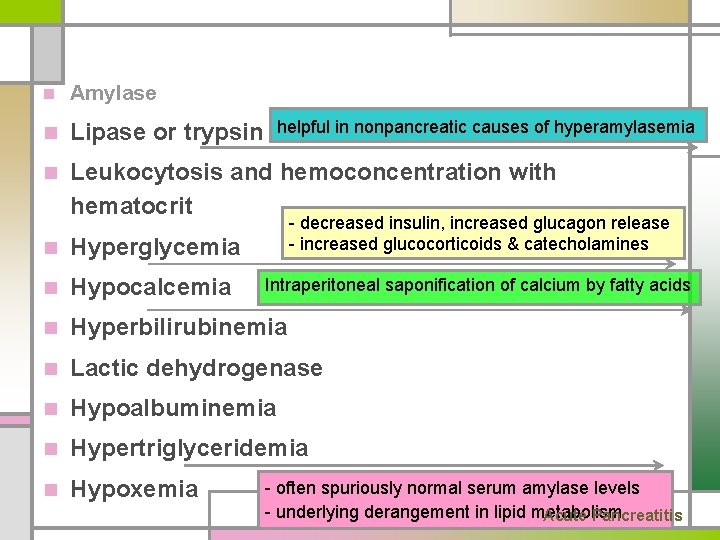

n Amylase n Lipase or trypsin n Leukocytosis and hemoconcentration with hematocrit helpful in nonpancreatic causes of hyperamylasemia n Hyperglycemia - decreased insulin, increased glucagon release - increased glucocorticoids & catecholamines n Hypocalcemia Intraperitoneal saponification of calcium by fatty acids n Hyperbilirubinemia n Lactic dehydrogenase n Hypoalbuminemia n Hypertriglyceridemia n Hypoxemia - often spuriously normal serum amylase levels - underlying derangement in lipid metabolism Acute Pancreatitis